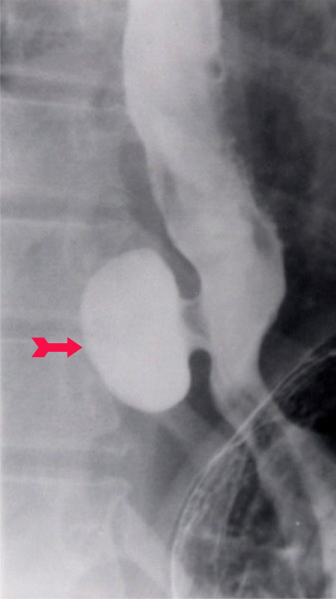

- צילום הוושט לאחר בליעת בריום והדגמת הסעיף מעל לסרעפת ובסמוך לה (תצלום 7.1).

- ב-CT חזה נראה סעיף מעל הסרעפת, את גודלו ויחסו לאיברים אחרים. בנוסף נוכל לקבל מידע על ממצאים פתולוגים נוספים בחזה ובבטן.